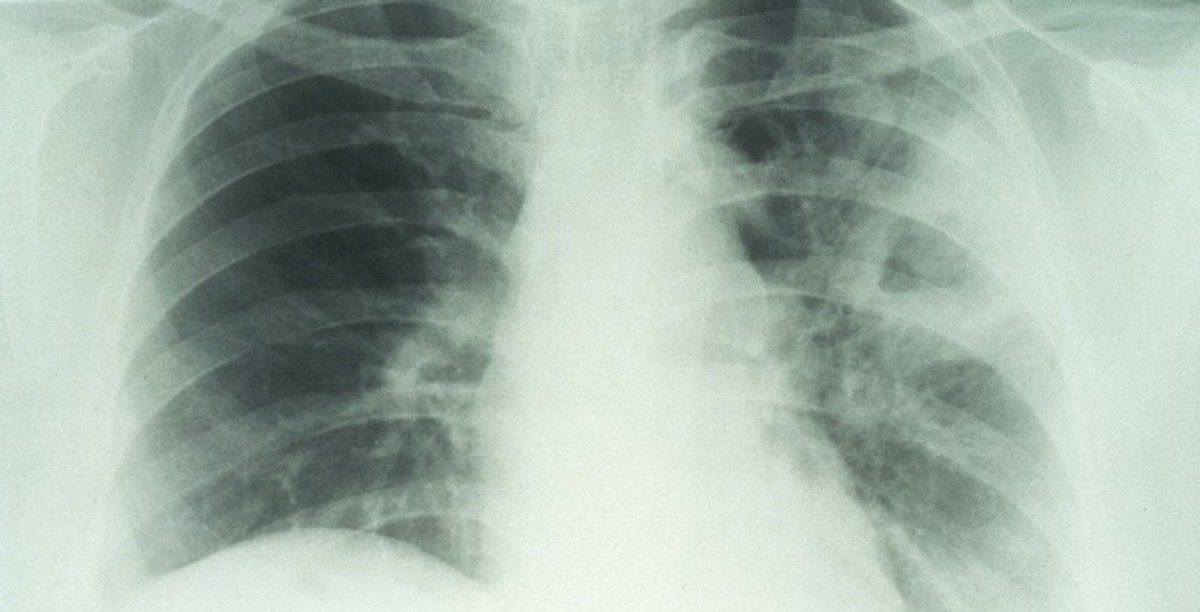

Το Mycobacterium tuberculosis, το βακτήριο που ευθύνεται για την φυματίωση, προσβάλλει τους πνεύμονες και στις περισσότερες περιπτώσεις το ανοσοποιητικό μας το κρατά υπό έλεγχο. Όταν όμως το ανοσοποιητικό εξασθενήσει, το βακτήριο παίρνει το… πάνω χέρι, εξαπλώνεται και προκαλεί εκδήλωση της νόσου. Η στρατηγική που το βοηθά να επιτυγχάνει τον στόχο του είναι η ικανότητά του να ξεφεύγει «εντοπίζοντας» τα σημάδια της επικείμενης επίθεσης των κυττάρων του ανοσοποιητικού όπως είναι η αλλαγή της οξύτητας –τα επίπεδα του pH.